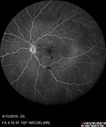

33 year old He noticed a new flash in the left eye. The flash started about 2 hours prior to the photos and he still notices it. The flash is in the center of the vision. The vision is not blurred. It's hard to tell because of the dilation. VA 20/12 OD and 5/200 OS. The vision remarkably improved to 20/16 within 1 month in the left eye. Blood tests showed a protein C deficiency.

Central retinal artery and vein occlusion - Protein C Deficiency 33 year old male571 views33 year old male with vision loss for 3 hours. VA 20/12 right eye, 5/200 left eye. He has a protein C deficiency. The left eye recovered vision in about 1 month to 20/16. FA shows very slow recirculation time.     (0 votes)